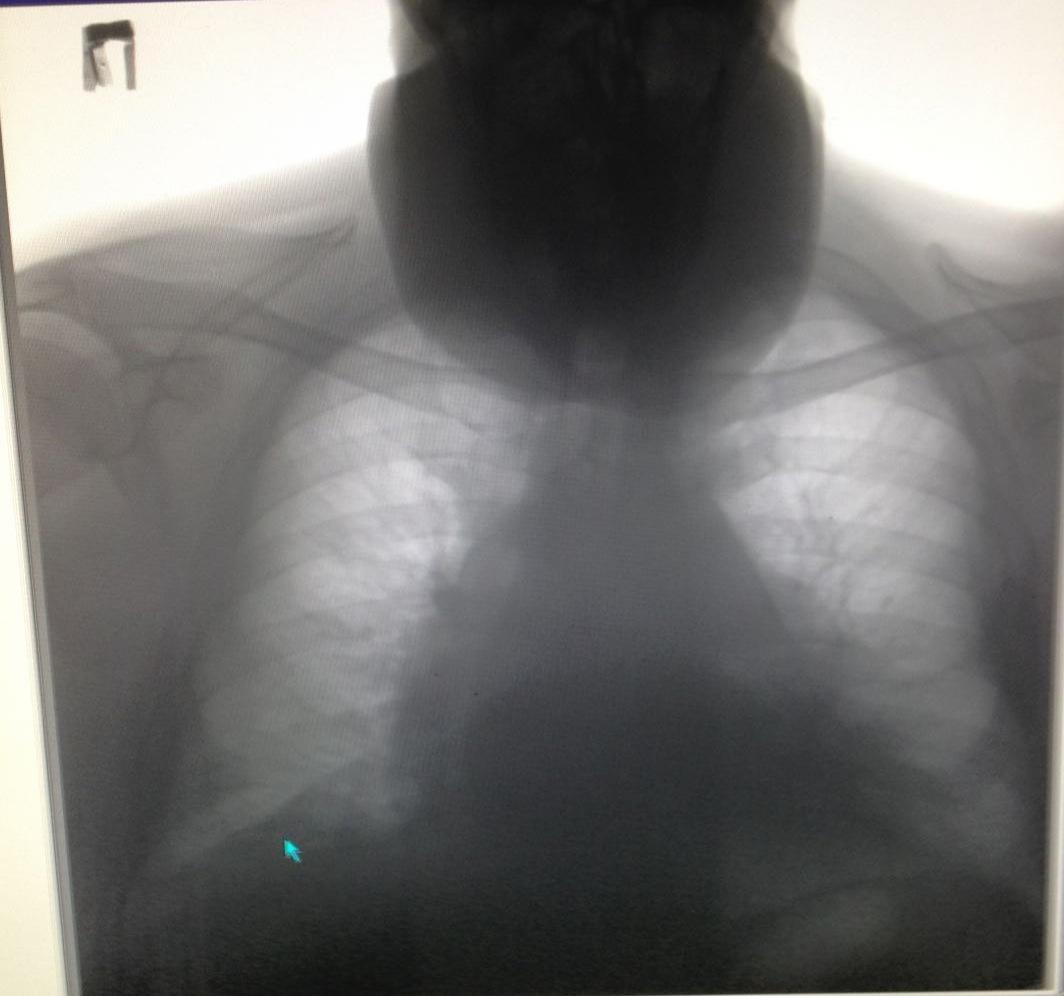

Зоб но на шее

Не обсуждалось